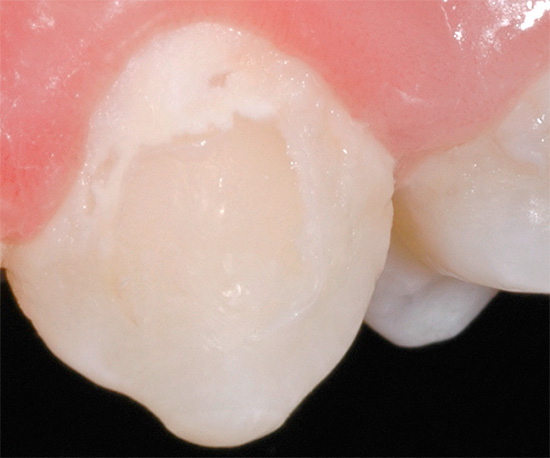

Se il dente fa male solo dall'azione di stimoli esterni (freddo, dolce, caldo, acido) e la polpa al suo interno non è influenzata dal processo infiammatorio, il medico pulirà la cavità cariata con o senza anestesia, risciacquare con antisettici e riempirlo. Tale dente viene di solito trattato in una visita.

Cosa farà il dottore se il dolore ai denti è dovuto alla pulpite?

Se, ad esempio, a causa della carie profonda, il "nervo" del dente è stato infettato, il medico tratterà tale dente in una o più visite. Innanzitutto, l'anestesia viene eseguita, una camera di polpa viene aperta con un trapano, il "nervo" viene rimosso, i canali all'interno della radice vengono puliti, lavati, sigillati e un riempimento viene posizionato sulla parte superiore del dente.